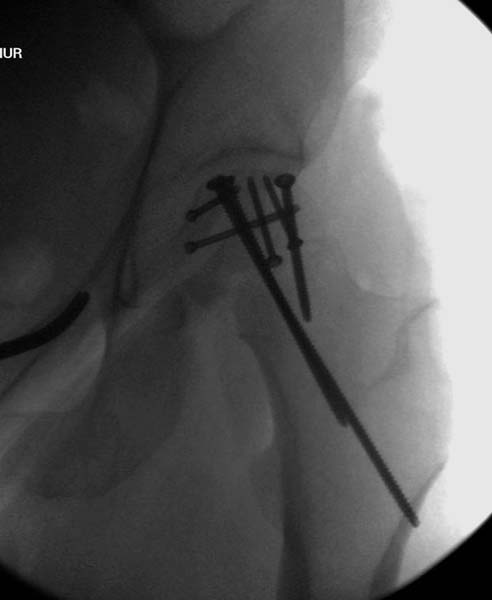

> Для решения проблемы дистальной блокировки компания DigiMed недавно

> предложила систему блокировки без рентгена. Пока в стране только два набора

> и только для антеградных гвоздей, но компания работает над созданием

> устроиства для других гвоздей тоже..

> Результат первых случаев показала отсутствие разницы между занятиями на

> муляжах, а также Workshop и с удивительной точностью вывел латерально над

> кожей специальное сверло. Дальше по сверлу тонкий направитель и проводится

> сверление каннюлированным сверлом....